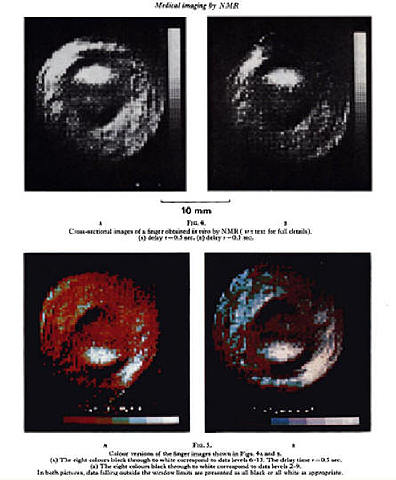

• Primera Imagen de resonancia magnetica, Un dedo

Primera Imagen de resonancia magnetica, Un dedo

Peter Mansfield y Paul Lauterbur posteriormente siguieron contribuyendo al desarrollo de la RM, con gran número de artículos en la revista Physics in Medicine and Biology y en un artículo clásico, Mansfield y A.A. Maudsley en 1977 publicaron la primera imagen seccional de una región de la anatomía humana, un

dedo. P. Mansfield y P. Lauterbur fueron galardonados con el premio Nobel de Fisiología y Medicina de 2003